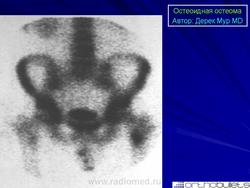

Внутрисуставная остеоид остеома, которая локализуется в пределах сустава, или вблизи от него, считается отдельной клинической единицей. Наиболее часто поражается тазобедренный сустав.

Голеностопный, локтевой, лучезапястный и коленный суставы поражаются намного реже.

Внутрисуставноя остеоид остеома встречается редко, и её клинические проявления могут быть нетипичными.

Пациенты жалуются на боль, которая не обязательно усиливается в ночное время, боль в суставе не облегчается приёмом салицилатов.

Боль в области сустава и суставной выпот могут внести свой вклад в «диагностическую путаницу».

Результаты визуализации внутрисуставной остеоидной остеомы резко отличаются от таковой при интракортикальной остеоидной остеомы.

При внутрисуставных остеоид остеомах реактивная кортикальная реакция минимальна, или отсутствует.